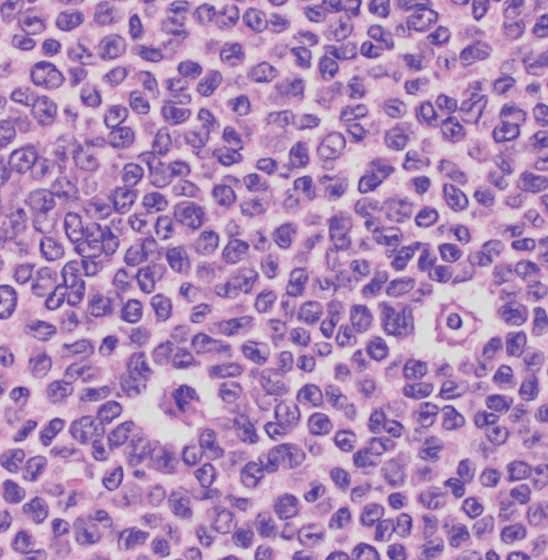

Tumors with coffee bean shaped nuclei

1. papillary thyroid carcinoma. 2. Granulosa cell tumor 3.Langerhen cell histiocytosis 4.Brenner tumor 5. Chondroblastoma